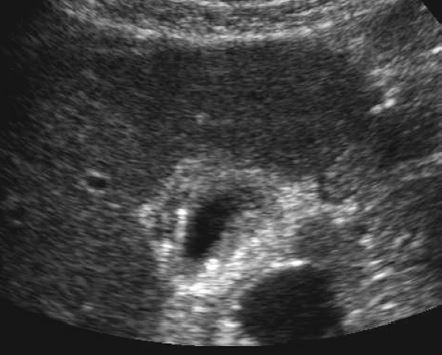

The gray-scale view shows a complex fluid

collection arising from the right kidney. In addition,

there is a simple-appearing, round, cystic structure

within the otherwise complex collection. The

power Doppler view shows flow in the apparent

cyst. All of these findings are consistent with a

pseudoaneurysm and adjacent hematoma.

Always put color Doppler on a “simple-appearing” cyst to make suer it is not something else!!!